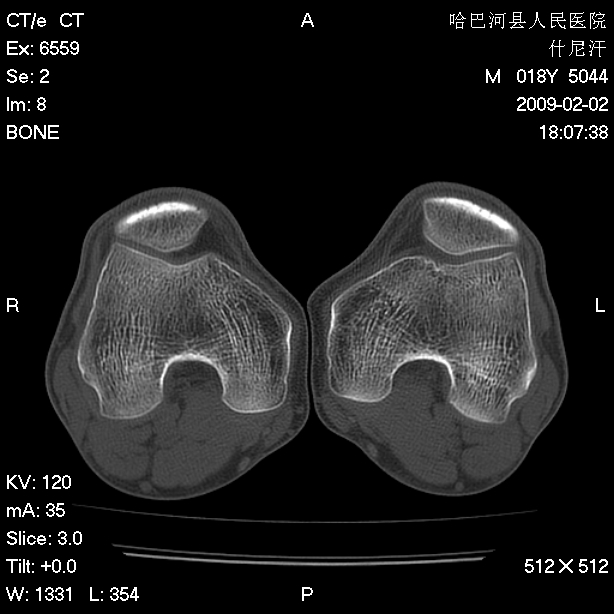

标题: CT17889:外伤后右膝关节反复疼痛3年余 [打印本页]

标题: CT17889:外伤后右膝关节反复疼痛3年余

ct未见明显异常。关节腔未见明显积液,半月板未见明显撕裂。但最好还是mri看看韧带及半月板情况。